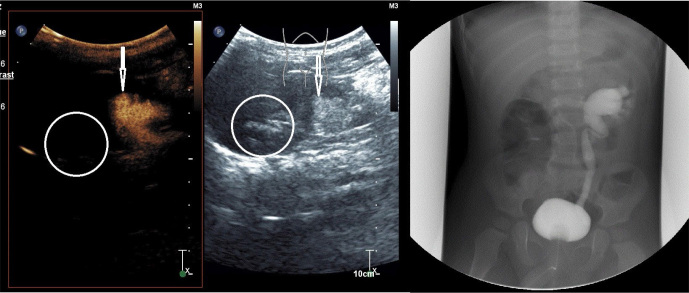

Conclusions: RBUS effectively diagnoses duplex kidneys with renal pelvic dilation, while ceVUS can further elucidate whether reflux occurs in the upper or lower moiety in cases of duplex kidneys with VUR. Compared to VCUG, both RBUS and ceVUS provide more intuitive diagnoses for duplex kidneys with VUR and ureterocele. Additionally, there is good consistency between ceVUS and VCUG in grading VUR. CeVUS is recommended as an initial evaluation method for patients suspected of having duplex kidneys associated with urinary tract infections.

Abstract Image